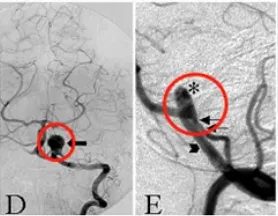

图1D:术前左侧VA造影显示大量血栓形成的VA-PICA动脉瘤的灌注部分(箭头)。图1E:术前左侧VA血管造影,VA-PICA动脉瘤合并巨大血栓形成,显示动脉瘤灌注部分(星形)和不同直径的左侧VA(箭头)和PICA(双箭头)。

图1F:磁共振血管造影显示VA-PICA动脉瘤部分血栓形成(箭头)。图1G:CT显示动脉瘤的血栓形成及部分钙化(箭头)。